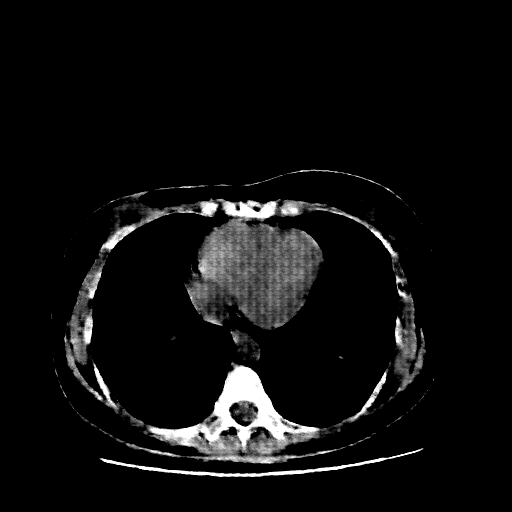

Image Grid

4Γ—3 grid: Rows show different image types (Original NATIVE, Reconstructed NATIVE, Original VENOUS, Generated VENOUS), Columns show windowing techniques (No Window, Lung Window, Mediastinum Window)

Original VENOUS CT scan

Mediastinum window (WL 40, WW 400 β†’ Low βˆ’160, High +240)